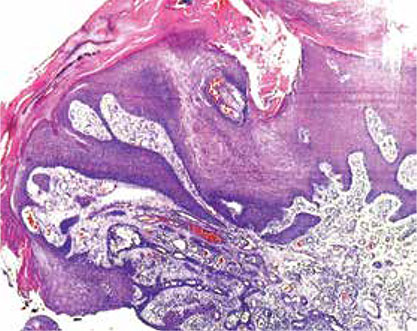

Haga usted el diagnóstico. Parte 1

Haga usted el diagnóstico. Parte 2